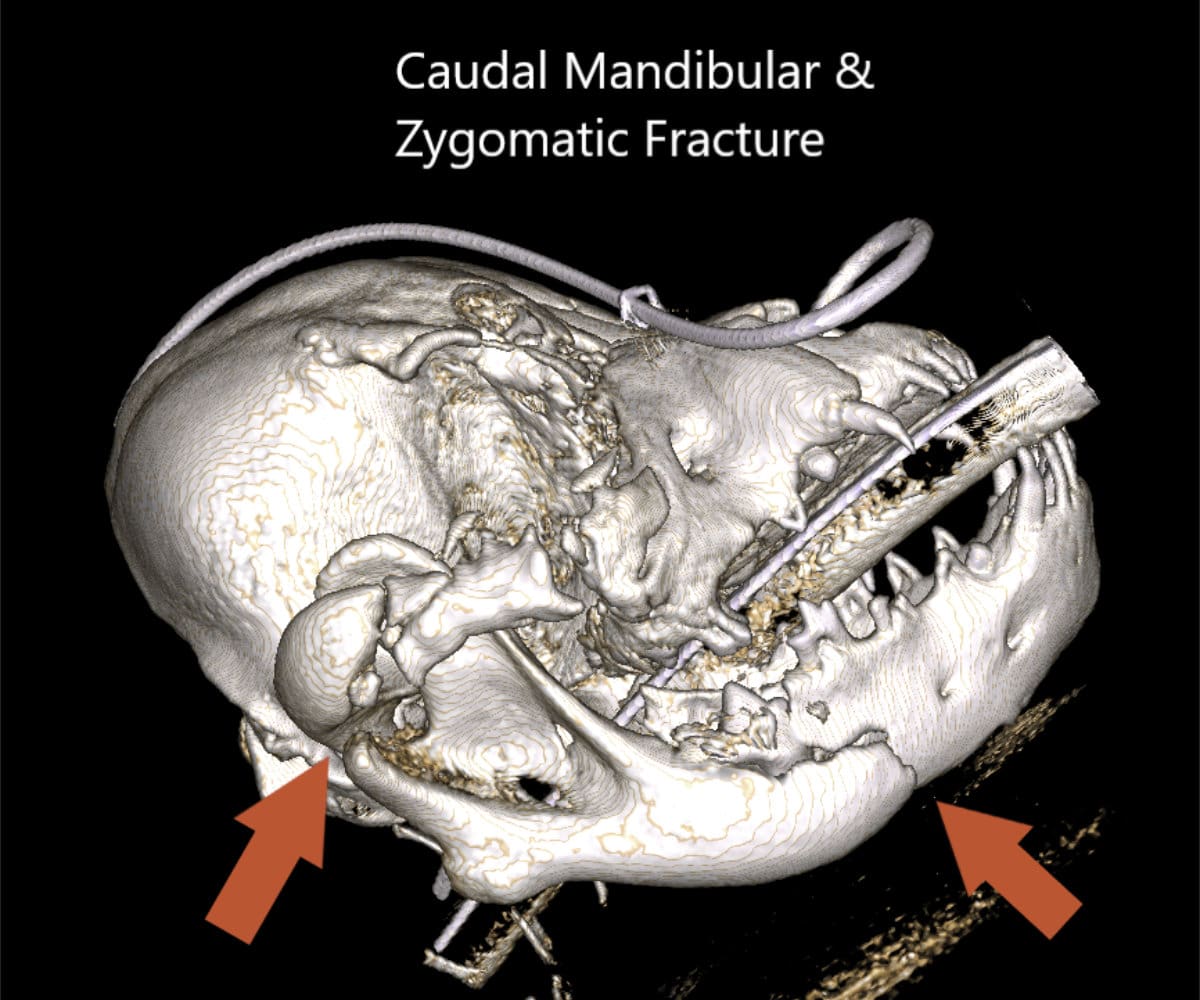

The advantages extend beyond diagnosis, as CBCT enables intricate 3D reconstructions of the skull, providing invaluable support to our doctors in the meticulous planning process for facial plating procedures.

Our CBCT VetCAT unit is easily rolled up to our treatment table and takes only 40 seconds to complete a scan. It has proven to be invaluable in the diagnosis and treatment planning for pets with periodontal, endodontic and cancerous disease conditions. It is also indispensable in the evaluating our trauma cases with jaw fractures.